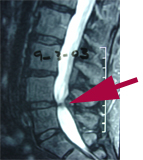

Cox® Technic Benefits Spinal Stenosis

Spinal stenosis is a common back pain diagnosis especially in older folks. The chiropractic technique Yorkville Chiropractic and Wellness Centre uses is called Cox® Technic Flexion Distraction. It is shown to be more effective than other conservative therapies to reduce pain and disability. (1) Experience the relief for yourself at your next Toronto chiropractic visit!